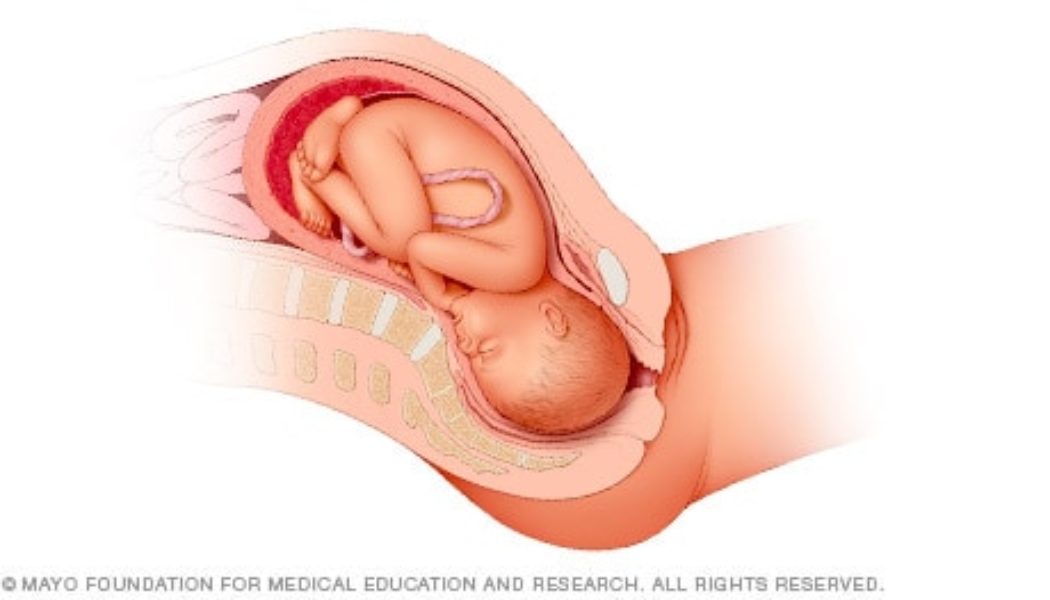

Head down, face down

When a baby is head down, face down, the medical term for it is the cephalic occiput anterior position. This the most common position for a baby to be born in. With the face down and turned slightly to the side, the smallest part of the baby’s head leads the way through the birth canal. It is the easiest way for a baby to be born.